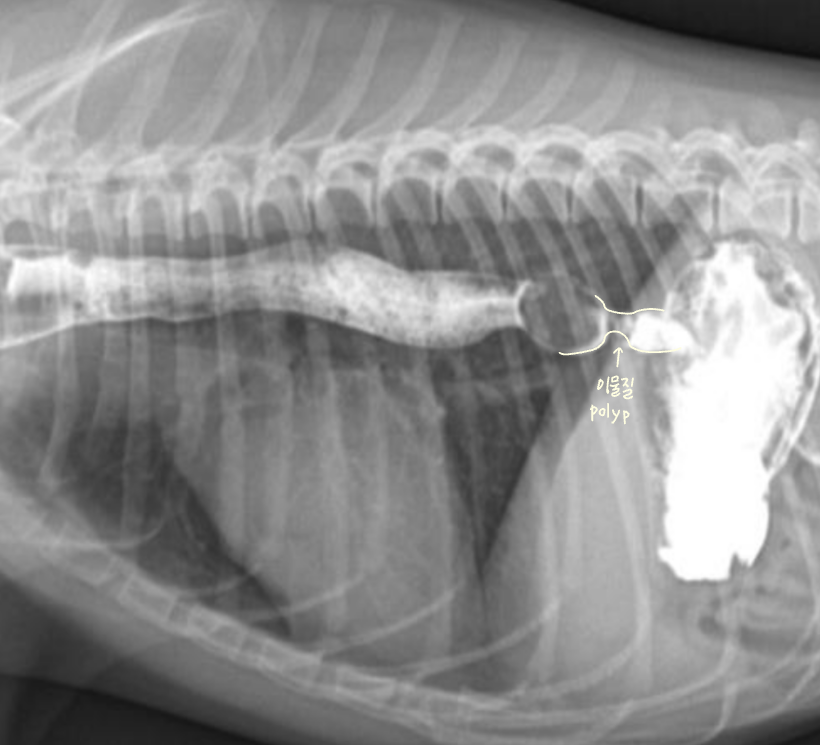

Intestinal tumor (์ฅ ์ข ์)

- ์ด์ง ์ ๋ฉ์ด๋ฆฌ๊ฐ ๋ง์ ธ์ง ์ ์์

- ๋ณต๊ฐ serosal detail ์ ํ

- ์๋ฒฝ, ์ฅ๋ฒฝ ๋นํ (์ ์๋ณด๋ค 2๋ฐฐ ์ด์ ์ฆ์ํ๋ฉด ์์ฌ)

- ์กฐ์ ์ ์ฅ๋ฒฝ ๊ฒฝ๊ณ๊ฐ ์ธํ๋ถํํจ (๋ด๊ฐ์ด ๊ฝ ์กฐ์ฌ์ ธ ์๊ธฐ ๋๋ฌธ)

- pseudoulcer sign (์ฃผ๋ณ ์ผ์ฆ์ผ๋ก ์ธํด ์ฅ์ด ์ญ๊ธํด์ ธ์ ์ฃผ๋ฆ ์ฌ์ด์ ์กฐ์์ ๊ฐ ๋จ์)

- ์ข ์์ ์ผ๋ฐ์ ์ผ๋ก ๊ทผ์ธต์์ ์์๋จ.

| ๋์ฌ์์์ ์ฆ์์ด ๋ํ๋ ์ฅ๋ฒฝ์ด 360๋๋ก ๋นํ๋๋ฉด์ ์ ์ฒด์ ์ผ๋ก ์ข์์ง โ ์กฐ์์ ์ ์ฃผํ์ด ๋๊ฒจ ๋ถ๋ฆฌ์ฒ๋ผ ๋ํ๋๋ ๋ชจ์ ![]() ![]() | Intestinal mass 1. lymphoma 2. MCT |

โ Final Dx ๋ด๋ฆฐ ์ผ์ด์ค

| Duodenal adenocarcinoma | Gastric lymphoma | FIV-induced lymphoma | Intestinal lymphoma |

|---|---|---|---|

| ๊ธฐ๋ ฅ์ ํ, ๊ตฌํ , ์ฒด์ค ๊ฐ์ Melena (โ ์๋ถ ์ํ๊ธฐ ์ถํ) mass ๋ง์ ธ์ง | chronic vomiting | Constipation, weight loss | Diarrhea, anorexia |

| ์ฅ๋ฒฝ ๋นํ (duodenum ๋๊ป 2๋ฐฐ ์ด์) Filling defect (์ฅ ๊ฒฝ๊ณ ์ธํ๋ถํ) Pseudoulcer sign | ์๋ฒฝ์ด ๋นํ๋๊ณ gas๊ฐ ์ฐธ. | ์ฅ๋ฒฝ ๋นํ | ์ฅ๋ฒฝ ๋นํ |

![]() ![]() | ![]() ![]() | ![]() | ![]() ![]() |

โ ๊ณจ๋ฐ๊ฐ ๋ด์์ ์๋ mass

- 4๊ฐ์์งธ ์ฌํ ๋ณ๋น + ์์๋ถ์ง, ์ฒด์ค ๊ฐ์, ๊ฐํ์ ๊ตฌํ ๋ก ๋ด์.

- Mass๊ฐ ๊ณจ๋ฐ๊ฐ ์์์ ์๋ผ๋ฉด ๊ฒฐ์ฅ๊ณผ ์๋๋ฅผ ๋ฐ์ด๋ด๊ณ , ์ ์ฑ ๋ณ๋น๋ฅผ ์ ๋ฐํจ.

- Leiomyoma๋ก ์ง๋จ๋จ.

โ ๋ด๊ฐ ์์ชฝ์์ ์๋ mass

- ๊ณจ๋ฐ๊ฐ๊ณผ ๋ฌ๋ฆฌ ๋ณต๊ฐ์๋ ์ฌ์ ๊ณต๊ฐ์ด ์์ด, ๋ด๊ฐ ๋ฐ๊นฅ์์ ์๊ธด mass๋ผ๋ฉด ๊ธธ์ ๋ง์ง ์์.

- ๊ทธ๋ฌ๋ ๋ด๊ฐ ์์ ์๊ธด mass๋ผ๋ฉด ๋ถ๋ณ์ด ๊ณ์ ์ถ์ ๋จ.

- ์กฐ์์ ๋ ์ผ์ ํ ๋๋น๋ก ํต๊ณผํ์ง ๋ชปํ๊ณ ๋งํ.